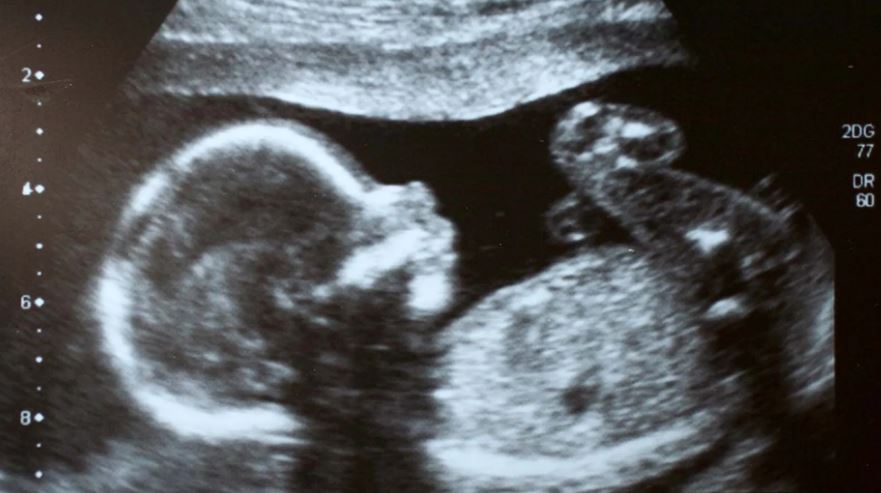

Sipas Bibliotekës Kombëtare të Mjekësisë të SHBA-së, gishtat e këmbëve të një foshnje të palindur mund të shihen dhe mushkëritë, veshët, sytë, krahët dhe këmbët e tij fillojnë të formohen përpara fundit të tremujorit të parë. Midis nëntë dhe 12 javësh pas konceptimit, fytyra e foshnjës formohet mirë, shfaqen organet gjenitale dhe thonjtë shfaqen në gishtat e duarve dhe këmbëve.